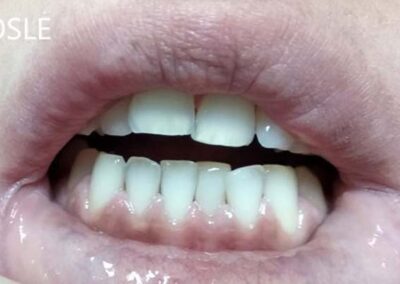

Slučaj 2

Pacijent je bio nezadovoljan estetikom svojih zuba, bojom i njihovim nepravilnim položajem. Sa obe strane zubnog niza nedostajale su četvorke.

Svakom pacijentu izlažemo sve opcije terapije. Nakon razgovora, pacijent se opredelio za protetsku terapiju metalokeramičkim mostom, nije bio zainteresovan za ortodontsku.

Urađen je metalokeramički most poštujući morfologiju svih zuba u frontu, uz maksimalnu gracilnost incizalnih ivica na sekutićima, što je pojačalo zadovoljavajući estetski efekat.